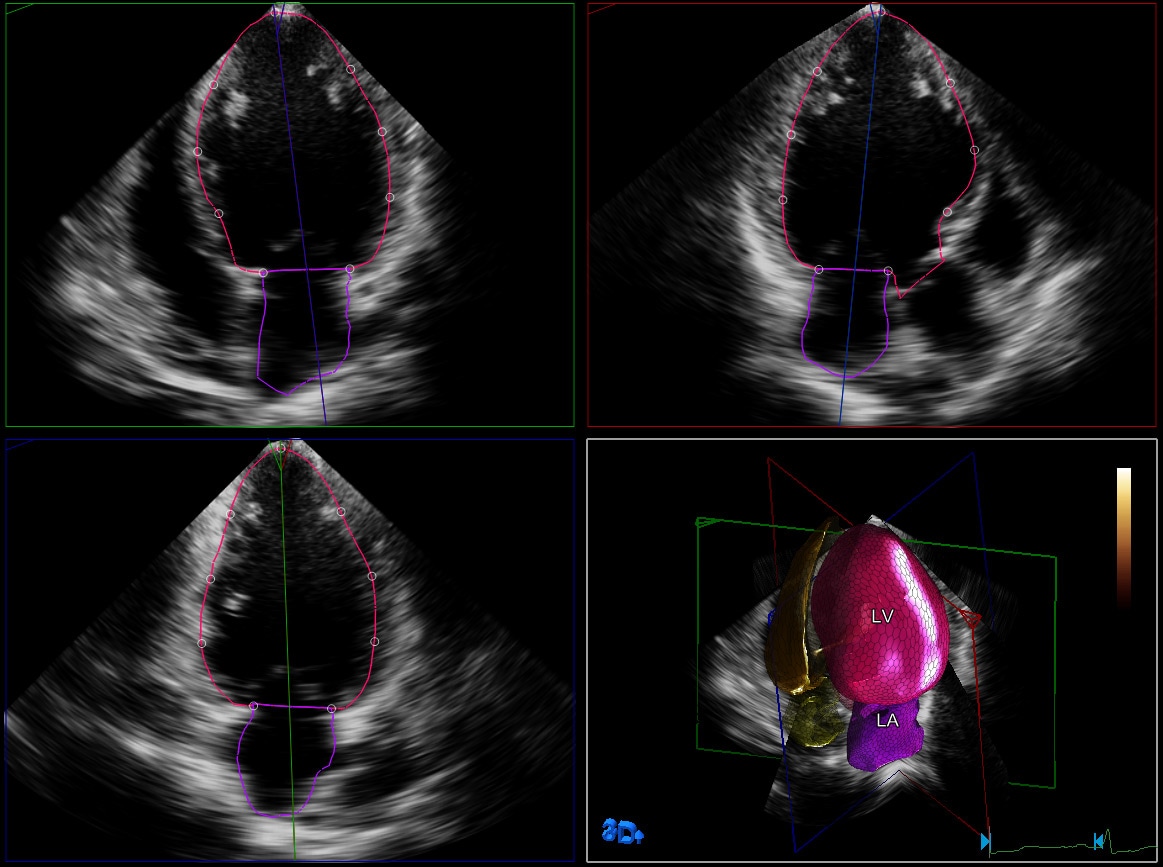

HeartModelA.I. es una herramienta 3D que puede ofrecer fracción de eyección (FE) reproducible robusta en solo unos segundos. Esta aplicación intuitiva y validada está diseñada para entregar la confianza de una cuantificación cardíaca que se adapta al flujo de trabajo cotidiano. HeartModelA.I. ofrece cuantificación 3D sencilla y rápida de la cámara cardíaca, mientras computa simultáneamente los volúmenes del ventrículo izquierdo (VI) y la aurícula izquierda (AI) desde un único bucle de volumen. HeartModelA.I. además de ofrecer cuantificación del VI, es la única herramienta validada para proporcionar volúmenes de la aurícula izquierda. Permite la caracterización sencilla del volumen de la AI para obtener más información clínica, sin tiempo ni pasos adicionales. Se ha demostrado que el volumen de la AI es un indicador de resultados cardiovasculares.

Este estudio comparó la cuantificación entre HeartModelᴬᴵ 2D y 3D en vivo y demostró un 82 % de ahorro de tiempo para HeartModelᴬᴵ cuando se utiliza la capacidad automatizada y un ahorro de tiempo del 63 %, cuando se requirieron ajustes menores.

El estudio multicéntrico de Medvedofsky et al demuestra que la ecocardiografía 3-D con HeartModelA.I. es exacta y reproducible.